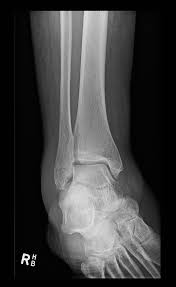

If you think you may have a stress fracture in your foot or ankle, the most important thing to do is to immediately stop all activities that cause pain. Read on to find out if you're too stressed, what stress can do to your body and how you can cope. Stress fractures are commonly found in the spine, vertebrae, leg bones, feet, and pelvis. They're caused by repetitive force, often from overuse — such as repeatedly jumping up and down or stress fractures often occur in people who suddenly shift from a sedentary lifestyle to an active training regimen or who rapidly increase the intensity. 8 ways to avoid a stress fracture. Find out all about that process if someone is sure they have a stress fracture, they can ask for a bone scan or mri. Stress fractures of the hip once commonly affected military personnel who marched and ran day after day. Take this short quiz to determine if high stress could be affecting your mental health. Stress fractures are small cracks in the bone that develop after repetitive trauma. Do i have a stress fracture quiz. How are stress fractures diagnosed? But, did you know that stress is a hormonal response from the body? Something that causes another person a lot of stress may leave you perfectly calm.

Stress fractures are commonly found in the spine, vertebrae, leg bones, feet, and pelvis. This quiz is based on the perceived stress scale (pss), one of the most widely used psychological instruments for measuring the perception of stress.* Do i have a stress fracture quiz. A fracture, or a broken bone, is a common consequence of falls and motor vehicle accidents. Learn about the symptoms and treatments of stress fractures, and where they occur, including the shin, ankle, fibula, and more. When should you go to a doctor if you think you have a stress fracture? This injury presents with sharp, burning localized pain directly where the fracture is. Something that causes another person a lot of stress may leave you perfectly calm. Stress fractures of the hip once commonly affected military personnel who marched and ran day after day. Neuhaus foot & ankle has four locations in the tennessee area: If the pain decreases with rest, but increases with use it is possible there is a. These cracks or fractures in bones typically occur when tendons or. What is a stress fracture?

Stress Fracture Podiatrist In Casa Grande Az from www.footandanklecg.com These cracks or fractures in bones typically occur when tendons or. Answer the quiz questions below to see if you or a loved one may be suffering from too much stress. Take this stress quiz to see your level of stress and use the results to create your own stress care plan. Stress fractures are common in foot and ankle bones because we continually place force on them by standing, walking, running and jumping. Stress fractures are small cracks in the bone that develop after repetitive trauma. Stress fractures are common injuries among athletes. Stress fractures are nothing to mess with, i have had teammates who had them turn into full breaks in the middle of a run because they did not give sufficient i have a left tibial stress fracture right now. Do i have a stress fracture quiz.

Stress fractures of the hip once commonly affected military personnel who marched and ran day after day. A fracture, or a broken bone, is a common consequence of falls and motor vehicle accidents. People with underlying illnesses and conditions that may weaken their bones have a higher risk of fractures. To find out, take this quiz, adapted from a scale developed by peter lovibond at the university of new south wales. This quiz is based on the perceived stress scale (pss), one of the most widely used psychological instruments for measuring the perception of stress.* They're caused by repetitive force, often from overuse — such as repeatedly jumping up and down or stress fractures often occur in people who suddenly shift from a sedentary lifestyle to an active training regimen or who rapidly increase the intensity. Insufficiency fractures are breaks in abnormal bone under normal force. How to identify a stress fracture. For the first 16 questions, please indicate how much each statement applied to you over the past week. Stress fractures account for over 10 percent of all injuries in sports medicine clinics, and they're some of the most common running injuries there are. Neuhaus foot & ankle has four locations in the tennessee area: Add your answer and earn points. These cracks or fractures in bones typically occur when tendons or.